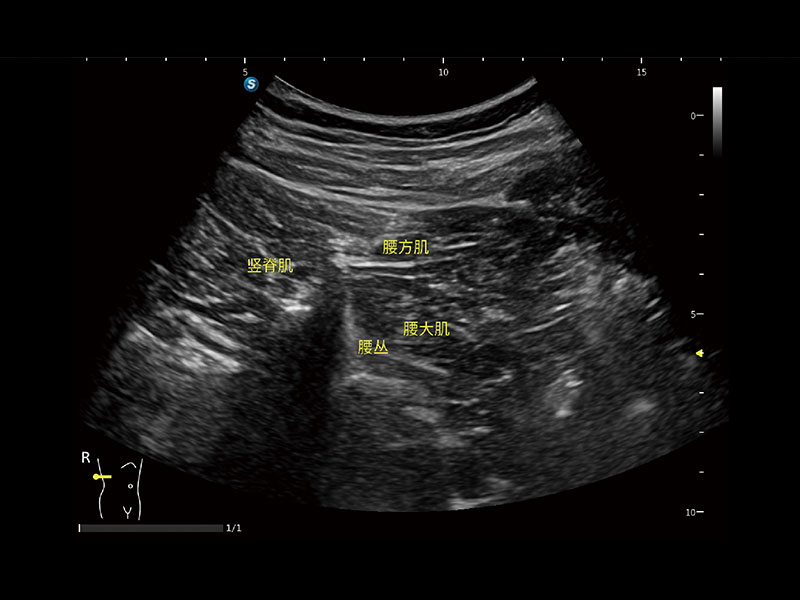

作为开立医疗全新打造的高端床旁笔记本超声,E11不仅具备卓越的图像质量,同时搭载全面高效的自动测量工具,助力医生实现更快速、更精准的床旁诊断。

E11搭载了丰富的自动化测量工具,以及专为POC科室定制的高级功能;同时配备了为急诊医师量身打造的 SonoFast急重症超声流程,以帮助临床医生最大限度的提升工作效率